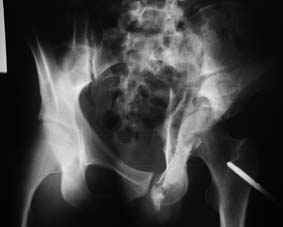

Уважаемые коллеги! Хотелось бы услышать совет по тактике лечения представлленого больного.Поступил после лечения в одном изотделений области. Травма 2,5 месяца назад. После выведенияиз шока был произведен остеосинтез перелома бедра, предплечья, до перевода к нам проводилосьвытяжение по оси шейки бедра за стержень, введенный в большой вертел. На сегодня деформацияригидна, клинически мобильности не определяется. Заранее признателен. P.S. Данный вид травм не включен в перечень "высокотехнологичных операций", направить длялечения по квотам Минздрава очень сложно.

Это обзорные и косые снимки

Привет, Леонид. Оскольчатый высокий двухколонный перелом в такие сроки трогать не надо, т.к. это про такие переломы сказано: "кто с ножом на Ж. пойдет тот в ней и останется...".